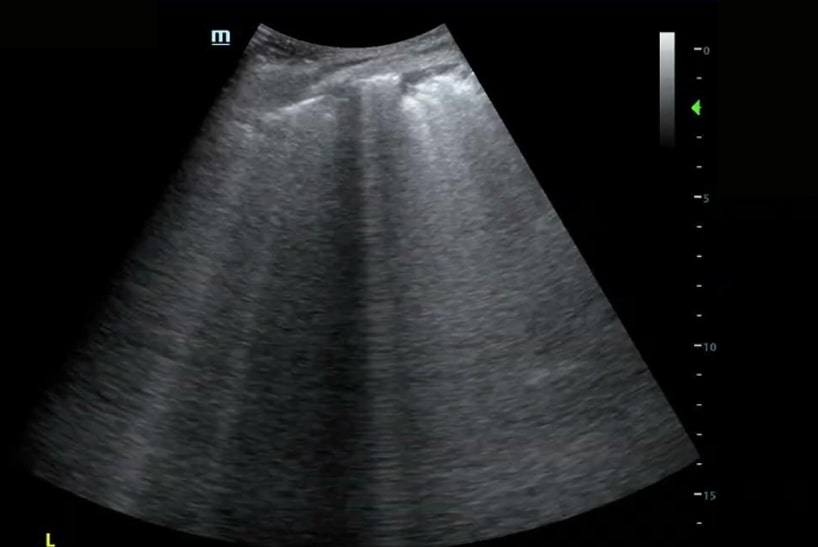

A significant portion of our current knowledge in lung ultrasound stems from Dr. Daniel Lichtenstein’s landmark paper in 1998. The paper discussed the use of artifacts to differentiate between pulmonary edema and COPD. Since that time some of the nomenclature was later redefined by Dr. Lichtenstein and what was then described as “roughly horizontal parallel reverberating lines” is now called A-lines and what was then called comet-tail artifact is now referred to as B-lines (defined as stretching below 16cm of depth). Additionally comet-tails artifact is now referred to as Z-lines and are defined distinct from B-lines and have no clinical significance:

Learning the “ABCs” of the lung can be helpful for interpretation of sonographic findings.

“A” or A-lines can be regarded as a normal lung artifact, but can also be seen in pneumothorax, asthma exacerbation, and COPD exacerbations in the right clinical context.

“B” or B-lines can be seen in pneumonia, pulmonary edema, interstitial lung disease, atelectasis, and acute respiratory distress syndrome (ARDS).

“C” or Consolidations are commonly seen in pneumonia and atelectasis and can be distinguished by clinical context and presence of static vs. dynamic air bronchograms (ABs).

Check out the sonographic images.

Bedside ultrasound revealed the expected diffuse B-lines in the bilateral posterior lower lung zones; however, it also found a consolidation in the left lower lung, seen here with the shred sign as well as a small pleural effusion. Therefore the patient was additionally treated for community-acquired pneumonia, which might not have been addressed without the use of point-of-care ultrasound (POCUS)!